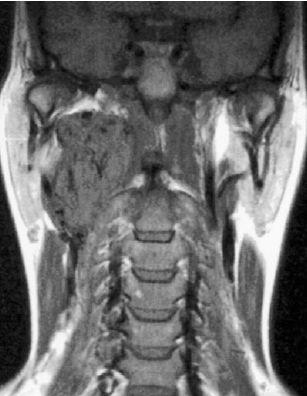

284 deelnemers

Een 33-jarige vrouw met een blanco voorgeschiedenis bemerkte een pijnloze zwelling rechts in de hals. Op een CT-scan met contrastmiddel werd een grote massa rechts in de hals gezien die de A. carotis interna en A. carotis externa uiteenduwde. MRI toonde multipele donkere gebiedjes in de tumor, die overeenkwamen met stromend bloed (zogenaamde ‘flow-voids’, soms beschreven als ‘peper-en-zoutaspect’).